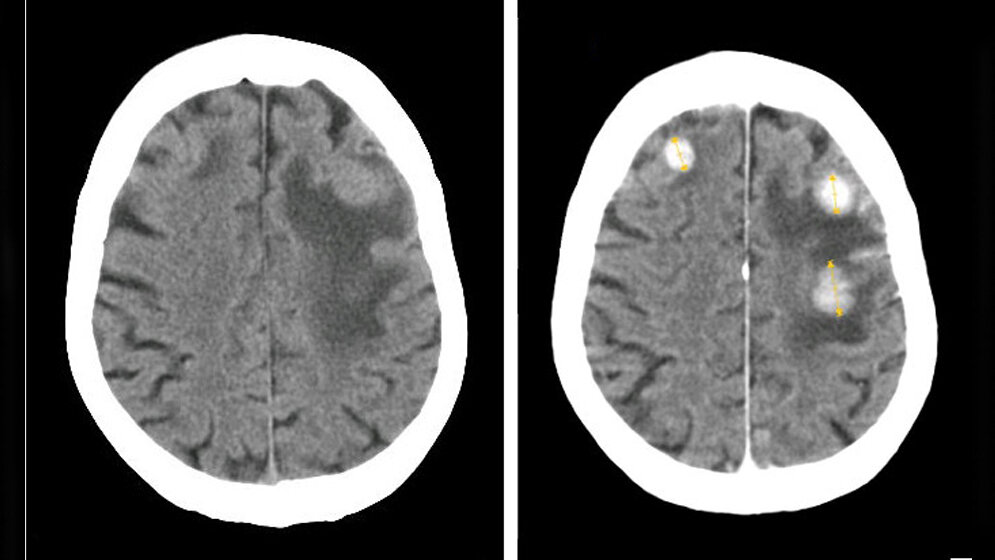

Wie effektiv stereotaktische Radiochirurgie und Ganzhirnbestrahlung im Vergleich sind, untersuchte eine retrospektive Studie, die im Juli 2016 im Fachmagazin Cancer publiziert wurde. Die Forscher analysierten Daten von Patienten mit nicht kleinzelligem Bronchialkarzinom oder Mammakarzinom, die zwischen 2007 (Diagnose NSCLC) bzw. 1997 (Diagnose Mammakarzinom) und 2009 an fünf großen US-Krebszentren entweder nach dem einen oder nach dem anderen Regime bestrahlt worden waren. 27,8% der NSCLC-Patienten (n = 400) und 13,4% der Patientinnen mit Mammakarzinom (n = 387) hatten nur eine stereotaktische Radiochirurgie zur Behandlung ihrer Hirnmetastasen erhalten. Bis auf wenige Ausnahmen hatten diese Patienten weniger als vier Hirnmetastasen von weniger als vier Zentimetern Durchmesser.

Mit statistischen Mitteln versuchten die Autoren, potenzielle Einflussfaktoren auszugleichen, aufgrund derer Patienten bevorzugt die eine oder die andere Bestrahlung bekommen hatten, etwa Zahl und Größe der Metastasen, Ausbreitung des Tumors, Jahr der Diagnose und behandelnde Klinik. Sie kamen zu dem Schluss, dass Patienten mit weniger als vier Metastasen im Gehirn, die kleiner sind als vier Zentimeter, länger überleben, wenn man primär auf die Ganzhirnbestrahlung verzichtet und stattdessen eine stereotaktische Radiochirurgie anwendet.